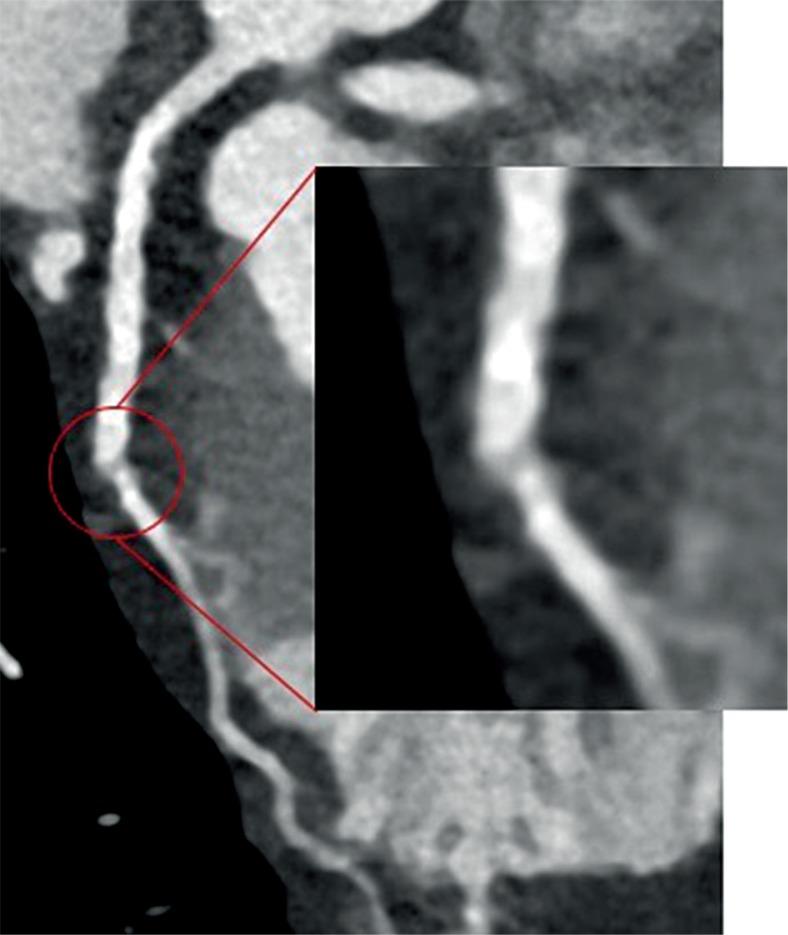

CCTA data were confirmed by ICA in 89% of subjects, and in 73% and 94% of patients with CS < 400 and ≥ 400, respectively. ICA confirmed 81% of calcific stenoses, 91% of mixed, and 67% of soft plaques. Both the dose exposure of patients with prospective acquisition (34) and the exposure of the whole population were significantly lower than the standard of reference ( < 0.001 and = 0.007).

CCTA with MBIR is valuable in detecting significant coronary artery stenosis with a solid reduction of radiation dose. Diagnostic performance was influenced by plaque composition, being lower compared with ICA for patients with lower CAC score and soft plaques; the visualisation of an intraluminal hypodensity could cause false positives, particularly in D1 and MO segments.

89%的受试者CCTA数据得到ICA证实,钙化积分<400和≥400的患者中分别有73%和94%得到证实。ICA证实了81%的钙化性狭窄、91%的混合性狭窄和67%的软性斑块。前瞻性采集患者的剂量暴露(34)以及总体人群的暴露均显著低于参考标准(<0.001和=0.007)。

采用MBIR的CCTA在检测显著冠状动脉狭窄方面具有重要价值,同时能大幅降低辐射剂量。诊断性能受斑块成分影响,对于钙化积分较低和软性斑块患者,与ICA相比诊断性能较低;管腔内低密度的显示可能导致假阳性,尤其是在D1和MO节段。